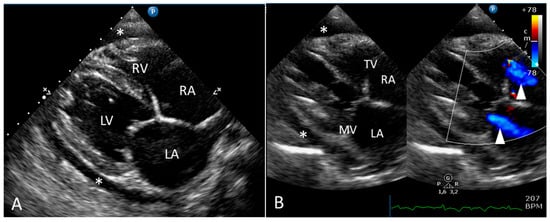

2.1. Clinical Report

2.2. Gross Pathology